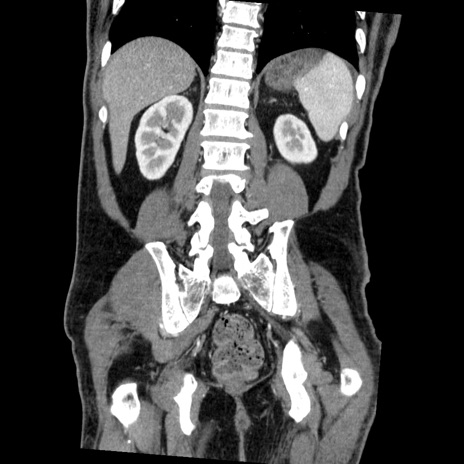

症例22(冠状断像)

【症例】50歳代男性

【主訴】腹痛

【現病歴】AVMからの被殻出血のため回復期リハ病棟入院中。 本日午後3時頃急に下腹部痛が出現した。

【既往歴】AVM、被殻出血、虫垂炎、高血圧

【身体所見】意識晴明、左半身不全麻痺、会話の理解は良好、36.5°C、腹部:膨隆、全体に板状硬、下腹部正中に圧痛点あり、反跳痛-、筋性防御不明、右下腹部にope scar

【データ】WBC 9400、CRP 0.06